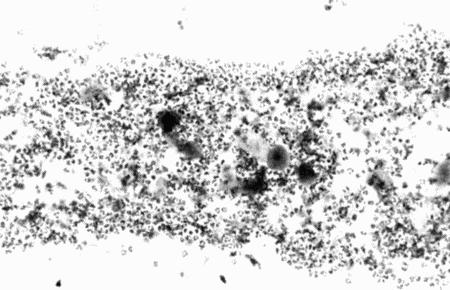

ВАГИНАЛЬНАЯ ЦИТОЛОГИЯ

Вагинальная цитология отражает гормональные изменения, происходящие в организме кошек (фиг. 2.2), особенно в период течки. Данный метод в племенном разведении кошек применяется реже, чем у собак, поскольку процедура может повлиять на ход цикла.

Во время фазы роста фолликулов в выделениях обнаруживаются поверхностные и кератинизированные клетки, наличие которых объясняется воздействием 17-β-эстрадиола. Процентное содержание безъядерных поверхностных клеток возрастает незначительно. В период фолликулярной фазы основной характеристикой вагинальных выделений является медленное сокращение количества клеток, содержащих ядро, промежуточных и базальных клеток. Однако указанные изменения у кошек менее выражены, чем у сук. Наиболее значимым индикатором активности эстрогена является осветление фона на предметном стекле, связанное с резким сокращением обломков разрушенных клеток и слизи. Содержание эозинофилов заметно ниже, чем у собак, эритроциты отсутствуют.

Для интерэструса характерно преимущественное содержание промежуточных клеток с небольшим включением базальных, парабазальных и кератинизированных клеток. В целом именно обломки клеток придают образцу характерный вид.

На стадии анэструса клеток немного, выделения содержат в основном слизь, базальные или парабазальные клетки с редким включением промежуточных клеток. В некоторых случаях присутствуют лейкоциты.

Вагинальная цитология применяется для установления или подтверждения фолликулярной фазы (проэструса или эструса). Обнаружение сперматозоидов вскоре после копуляции позволяет подтвердить факт вязки.

Фиг. 2.2.

Вагинальные выделения кошки (а). Выделения, типичные для фазы эструса. Большая часть клеток представляет собой безъядерные кератинизированные клетки или клетки с пикнотическим ядром. Присутствуют промежуточные клетки (b). Выделения, характерные для метэструса, — «течки», иногда наблюдаемой у кошек в конце эструса. Присутствуют поверхностные и промежуточные клетки, повышено содержание лейкоцитов. Этот короткий метэструс наблюдается в течение 24–48 часов (см. Приложение)